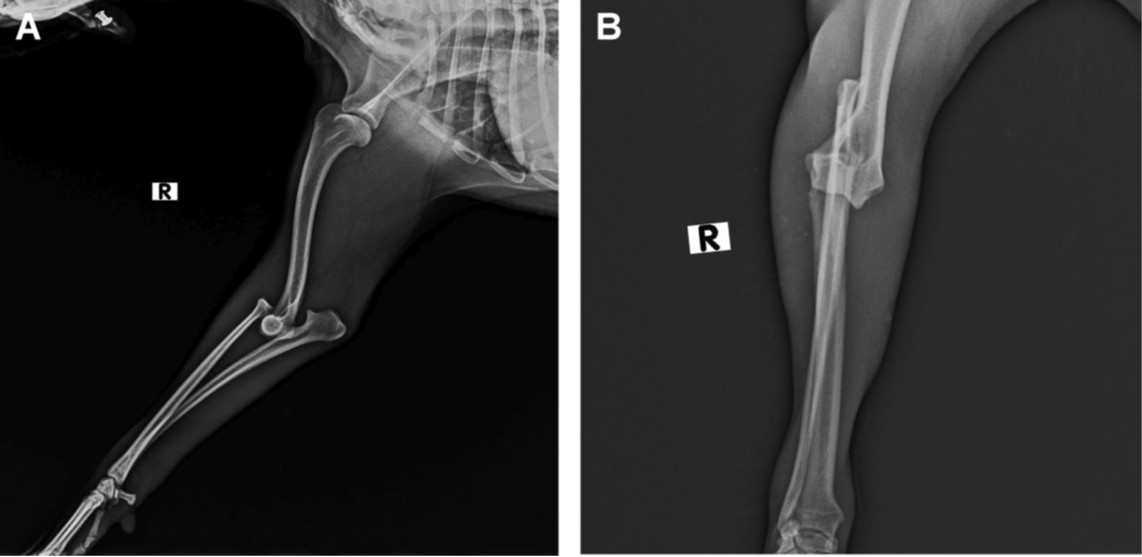

肘部准备进行手术,置于左侧卧位。手术区域使用4%氯己定和次氯酸进行消毒。为了避免在桡骨前侧对桡侧腕伸肌进行钝性分离,在尺骨后侧,肌肉密度较低的地方,做了一个小切口。

首先从尺骨近端后侧插入一根2毫米克氏针,穿过桡骨颈部。为了避免靠近关节,并确保桡骨有足够的骨量,克氏针的位置和水平在透视下被插入到环状韧带下方约1厘米处。随后放置了一枚20毫米、2.4毫米皮质螺钉,将脱位的桡骨固定到尺骨上(下图)。所有操作均在透视下进行,以评估肘关节的复位情况,并确认螺钉的准确位置。因此,脱位的桡骨头被成功复位并固定到尺骨上。在关节的伸展和屈曲操作中,未观察到再次脱位。

↑ 在透视引导下,通过微创方法复位右肘关节的术中图像。 (A, A’) 在透视引导下,显示从后侧切开暴露尺骨并指示螺钉放置位置。 (B, B’) 为了插入螺钉,首先使用2毫米克氏针从尺骨后侧钻孔,穿过尺骨到桡骨。 (C, C’) 插入一枚20毫米、2.4毫米皮质螺钉,以确保桡骨的稳定。